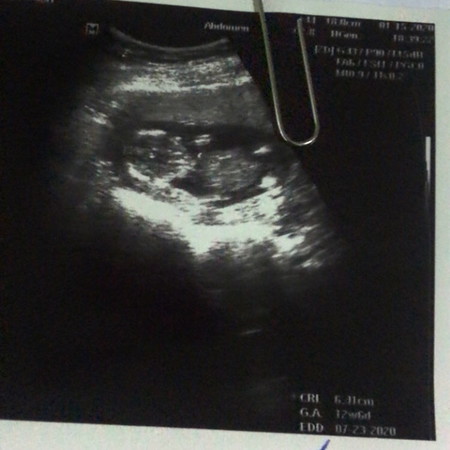

13 Weeks✌?

13 Weeks ท้องยังไม่ใหญ่ แอบกังวลเล็กน้อยค่ะ น้ำหนักก้อไม่เพื่ม กลัวลูกไม่สมบูรณ์ แต่ท้องแรกค่ะ แค่ซาวล์แล้วหัวใจเต้นปกติก้อสบายใจแล้วค่ะ❤️